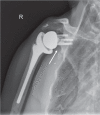

Since the introduction of reverse total shoulder arthroplasty (RTSA) in 1987 (in Europe) and 2004 (in the United States), the number of RTSAs performed annually has increased.Although the main indication for RTSA has been rotator cuff tears, indications have expanded to include several shoulder conditions, many of which involve dysfunction of the rotator cuff.RTSA complications have been reported to affect 19% to 68% of patients and include acromial fracture, haematoma, infection, instability, mechanical baseplate failure, neurological injury, periprosthetic fracture and scapular notching.Current controversies in RTSA include optimal baseplate positioning, humeral neck-shaft angle (135° versus 155°), glenosphere placement (medial, lateral or bony increased offset RTSA) and subscapularis repair.Improvements in prosthesis design, surgeon experience and clinical results will need to occur to optimize this treatment for many shoulder conditions. Cite this article: EFORT Open Rev 2018;3:58-69 DOI: 10.1302/2058-5241.3.170044.